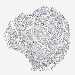

LUNG ADENOCARCINOMA (VALIDATION) - Interactive survival scatter ploti

The Survival Scatter plot shows the clinical status (i.e. dead or alive) for all individuals in the patient cohort, based on the same data that underlies the corresponding Kaplan-Meier plots. Patients that are alive at last time for follow-up are shown in blue and patients who have died during the study are shown in red.

The x-axis shows the expression levels (FPKM) of the investigated gene in the tumor tissue at the time of diagnosis. The y-axis shows the follow-up time after diagnosis (years). Both axes are complimented with kernel density curves demonstrating the data density over the axes. The top density plot shows the expression levels (FPKM) distribution among dead (red) and alive patients (blue). The right density plot shows the data density of the survived years of dead patients with high and low expression levels respectively, stratified using the cutoff indicated by the vertical dashed line through the Survival Scatter plot. This cutoff is automatically defined based on the FPKM cutoff that minimizes the p-score. The cutoff can be changed by dragging the vertical line or by entering a cutoff value in the square labeled "Current cut-off".

Under the Survival Scatter plot the p-score landscape (black curve; left axis) is shown together with dead median separation (red curve; right axis). Dead median separation is the difference in median mRNA expression between patients who have died with high and low expression, respectively. It is calculated as follows: median FPKM expression of dead patients with high expression - median FPKM expression of dead patients with low expression. This is intended to aid the user in visually exploring custom cutoffs and the associated p-scores and dead median separation.

Individual patient data is displayed and can be filtered by clicking on one or more of the category buttons on the top of the page. Categories describing expression level and patient information include: high, low, alive, dead, female, male and tumor stages. The scale of the x-axis can be toggled between linear and log-scale by clicking on the "x log" button. Mouse-over function shows TCGA ID, patient information and mRNA expression (FPKM) for each patient.

& Survival analysisi

Kaplan-Meier plots summarize results from analysis of correlation between mRNA expression level and patient survival. Patients were divided based on level of expression into one of the two groups "low" (under cut off) or "high" (over cut off). X-axis shows time for survival (years) and y-axis shows the probability of survival, where 1.0 corresponds to 100 percent.

MRPL41 is not prognostic in Lung Adenocarcinoma (validation)